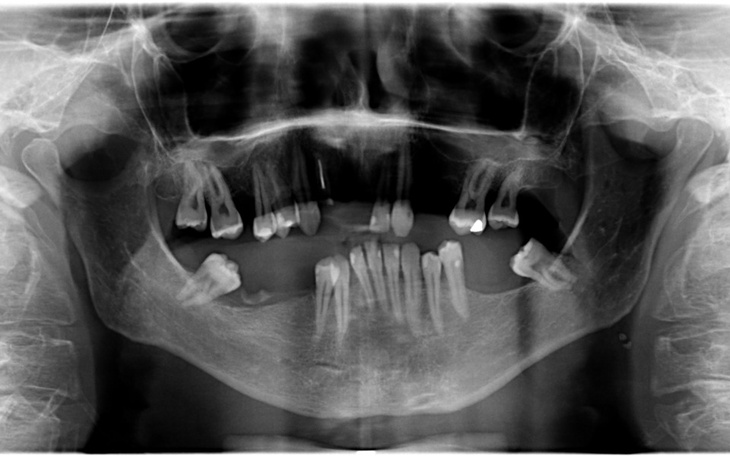

Każda wizyta u stomatologa to koszt od 200-300zł prywatnie. Mam do wyleczenia wszystkie zęby. Parę zębów ma do leczenia kanałowego.Jak widać na załączonym zdjęciu parę zębów utraciłem, ponieważ nie nadawały się do leczenia :( Pani stomatolog stwierdziła, że będzie przymusowa proteza w moim przypadku. Jak wiadomo jest to dość duży koszt.